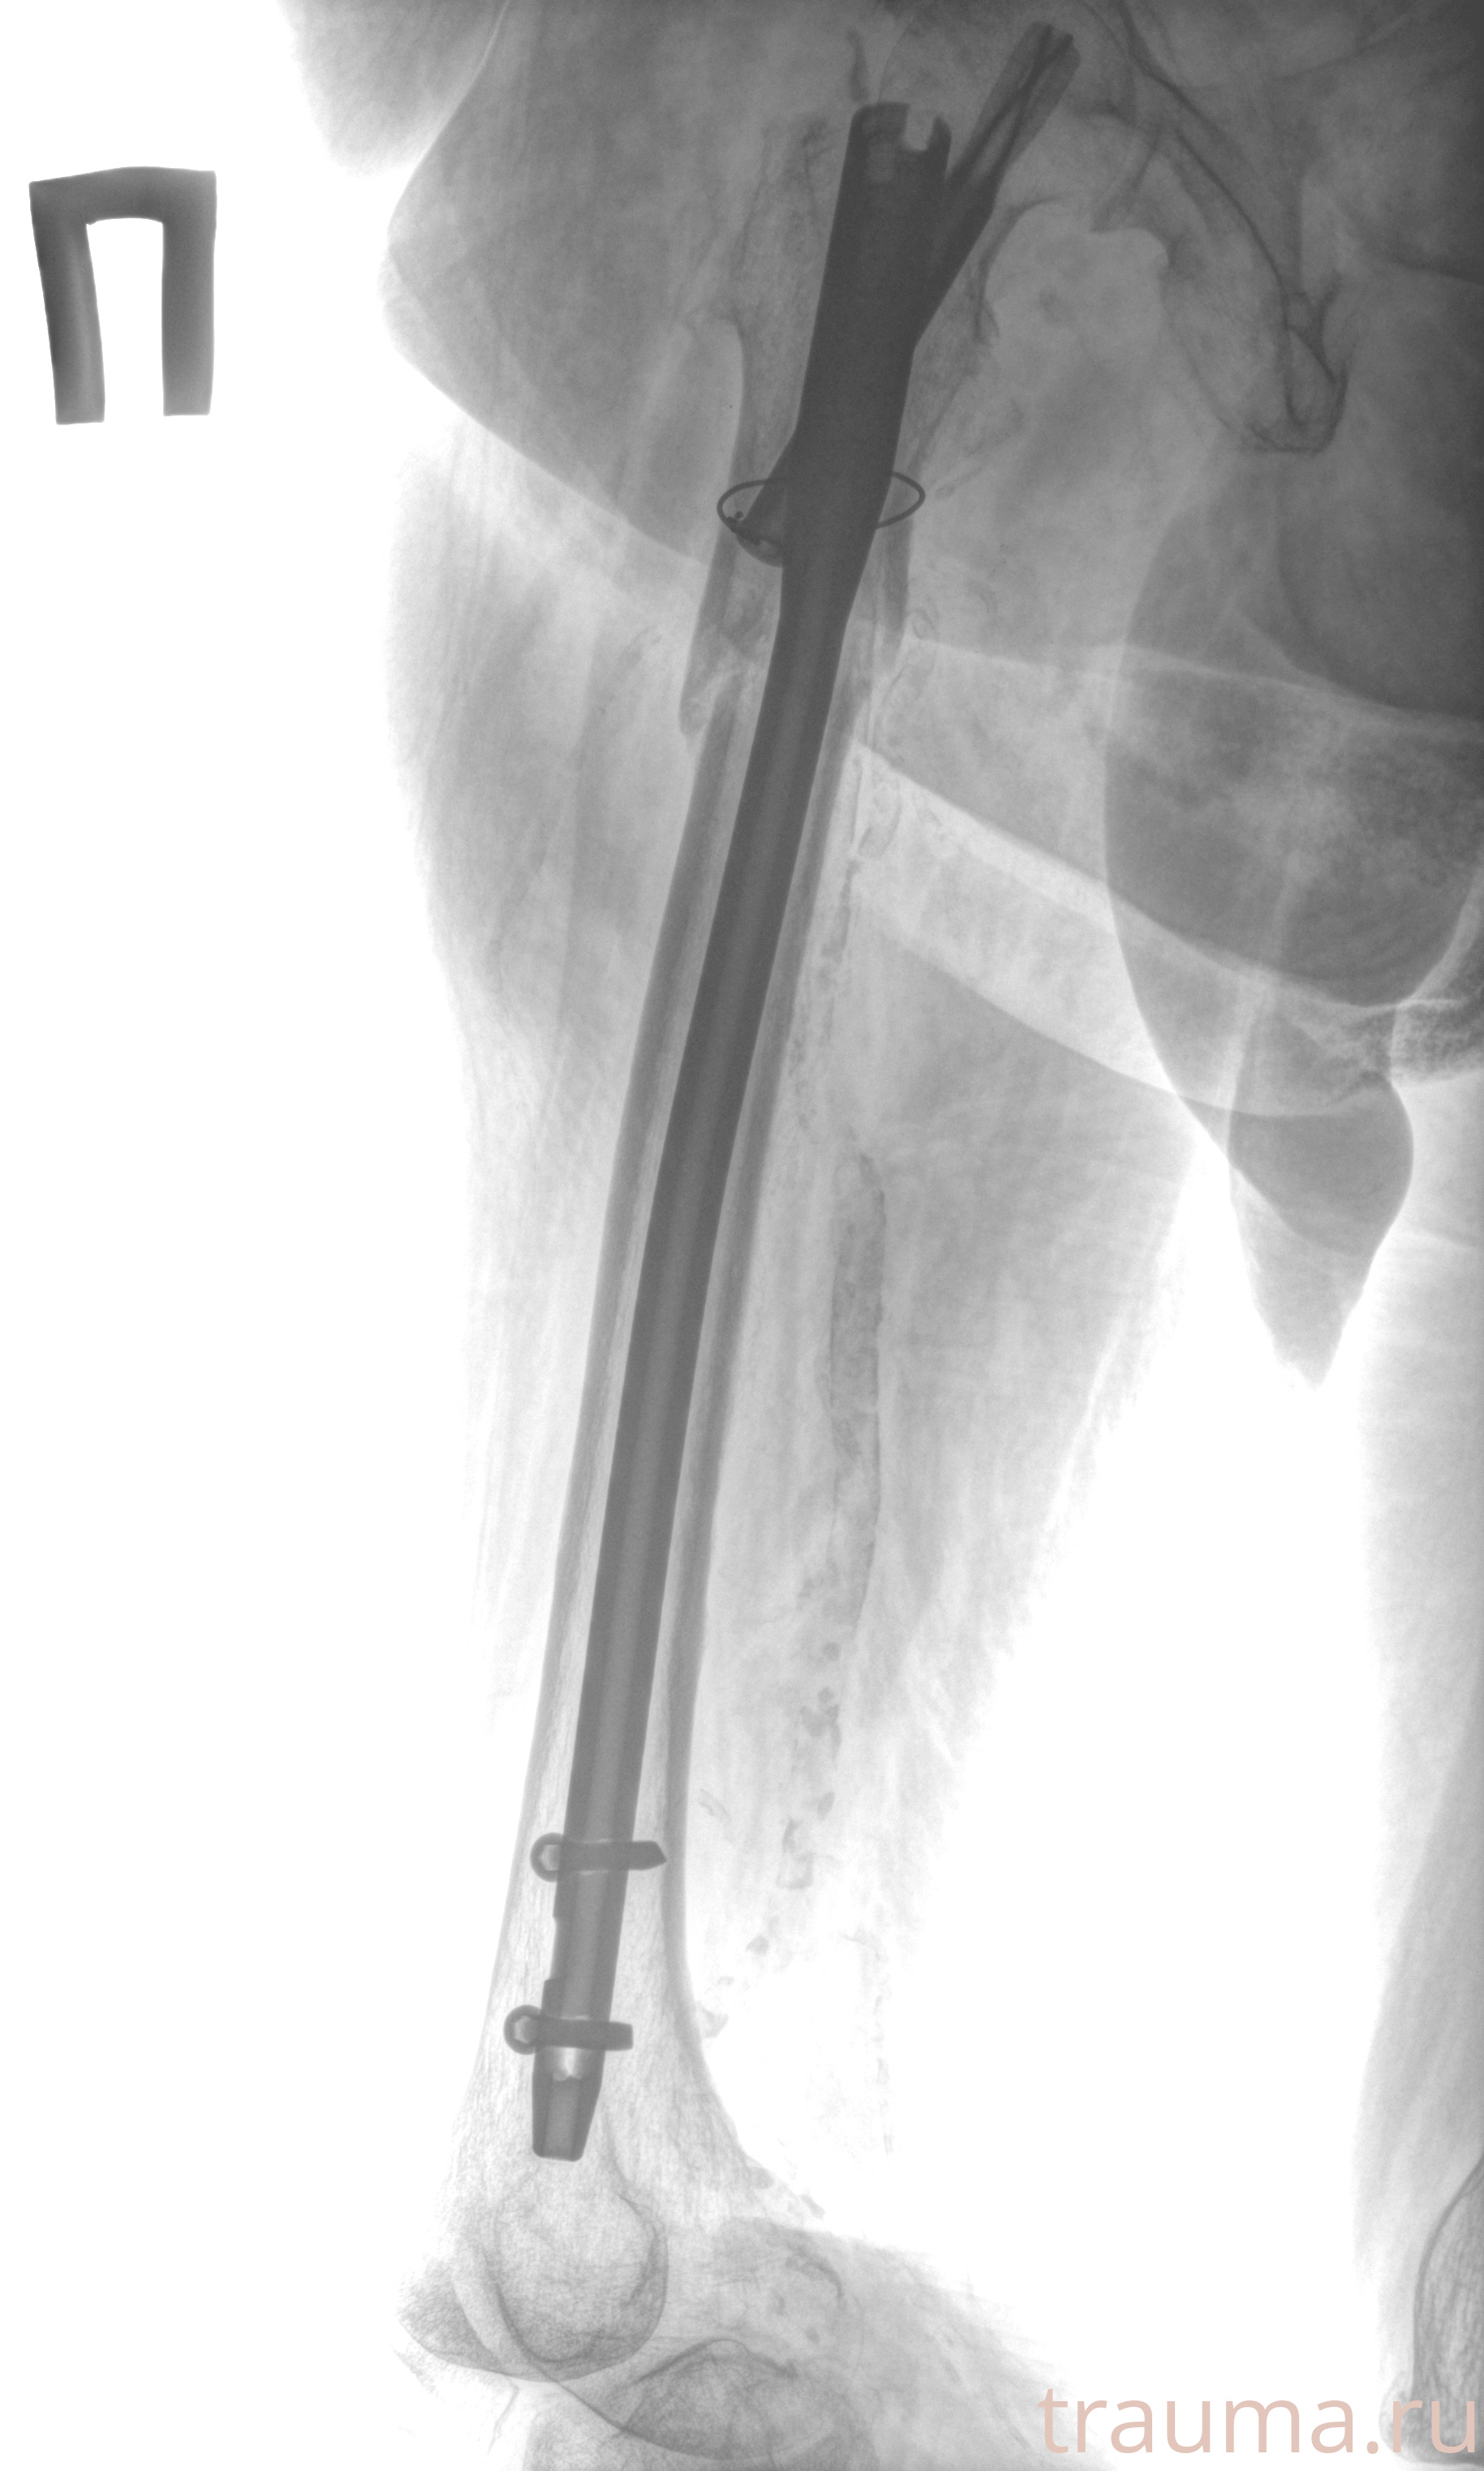

Рентгенограммы

Рентген на дому: по вашему адресу приезжает врач-рентгенолог, травматолог-ортопед с мобильным рентгеновским аппаратом, проводит диагностику травмы или заболевания, делает необходимые рентгенограммы, дает рекомендации по дальнейшему лечению. Получить качественные снимки в домашних условиях возможно благодаря уникальной методике, разработанной МосРентген Центром для института  Склифосовского